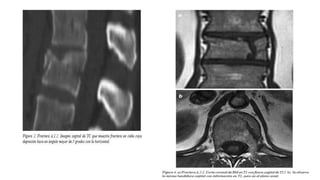

• Resonancia magnética: Examen de elección para observar los tejidos

blandos: medula, ligamentos, discos, hematomas.

• Tomografia computarizada:debe tomarse con cortes de 1.5 – 3 mm en los niveles de fractura y vertebras adyacentes. (mejor examen para evaluar estructuras óseas) • Resonancia magnética: Examen de elección para observar los tejidos blandos: medula, ligamentos, discos, hematomas.